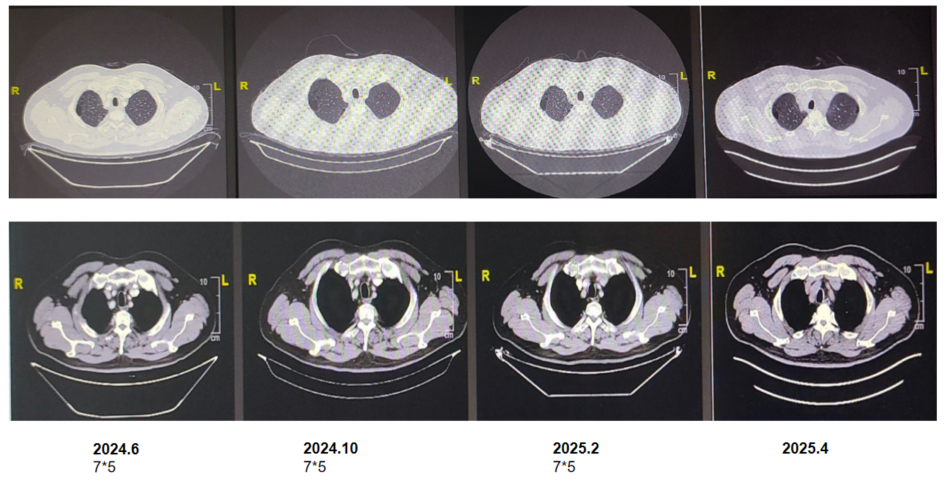

5)后续维持治疗与随访:2023年9月,MRI示骨盆仍有多处骨转移,右侧骶骨范围缩小,余同前。原本问题较为严重的髂骨病灶在放疗、免疫联合化疗、骨保护治疗的综合治疗下取得了良好的治疗效果,病灶大幅退缩,患者行动能力得到恢复;CT示右肺上叶肿瘤较前退缩,周围多发炎症较前减轻。右锁骨上淋巴结较前缩小。余双肺多发小结节,较前减少。两肺门及纵隔小淋巴结较前缩小。

2023年11月30日,CT示原右肺上叶纵隔旁肿块此次呈片状改变,右锁骨上淋巴结较前略缩小。部分椎体及肋骨局灶致密同前。

2024年3月29日,CT示右肺上叶纵隔旁片状影较前略减小,右锁骨上、两肺门及纵隔小淋巴结同前相仿,双肺肺大疱,两肺多发微小结节,部分椎体及肋骨局灶致密同前相仿。

2024年10月10日,CT示右肺MT复查,右肺上叶纵隔少许条状索影同前相仿,右锁骨上、两肺门及纵隔小淋巴结同前相仿,双肺肺大疱同前;部分椎体及助骨局灶致密同前相仿。

2025年4月15日,CT及PET/CT显示原发灶及全身多发转移淋巴结基本消退,全身多处骨转移灶亦明显好转,局部成骨性骨质改变,未见FDG代谢增高,提示骨修复。疗效评估:完全缓解(CR)。

结合III期临床研究的循证数据、患者治疗效果及患者自身治疗意愿,在免疫治疗+地舒单抗维持治疗~2年,达到CR且病情持续稳定后,综合考虑各方面因素,患者考虑暂停免疫治疗,末次免疫治疗时间为2025年6月3日,患者目前仍在随访中,持续CR。

该例55岁男性患者初诊为右肺癌伴骨多发转移及淋巴结转移。患者在骨放疗后接受4疗程含铂双药化疗+PD-1抑制剂治疗,疗效评估为SD。后行PD-1抑制剂联合化疗、骨保护药物地舒单抗治疗维持治疗,持续治疗近2年。目前,患者右肺原发灶及全身多发转移淋巴结基本消退,全身多处骨转移灶亦明显好转,局部成骨性骨质改变,疗效评估为CR。